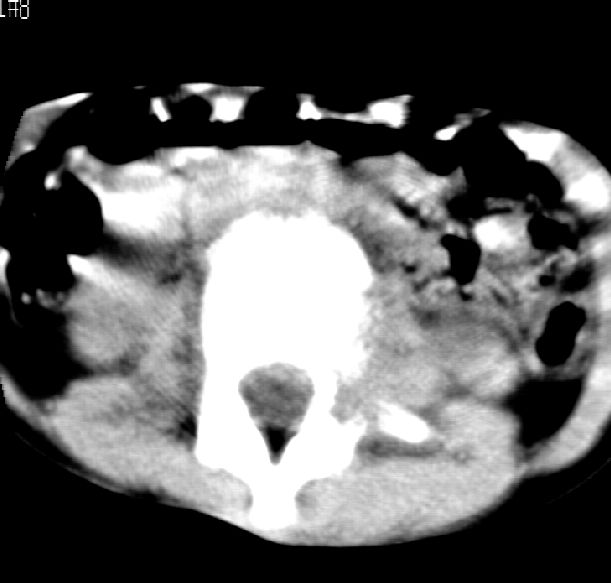

患儿女,11岁,因“腰痛,腰部活动受限10余天”入院。

10余天前,患儿无明诱因出现腰部疼痛,为持续性钝痛,以右侧为著,伴腰部活动受限,有发热,具体体温不详,无寒战、黄疸、盗汗、咳嗽,无尿频、尿急、肉眼血尿。

乍一看像是嗜酸性肉芽肿,但看到ct表现骨质破坏及软组织肿胀考虑结核可能性大,鉴别恶性肿瘤.

本例ct图像太不清楚了,而且不知道有没有传完,如果软组织病变只局限性于那几个层面的话多考虑嗜酸性肉芽肿,其次为其他肿瘤,结核椎旁软组织较广泛,在本例没有太典型表现,建议楼主(孩子父母吧)把所有的软组织窗图像(白色的那种)按顺序全部转上来.

考虑l3嗜酸性肉芽肿。